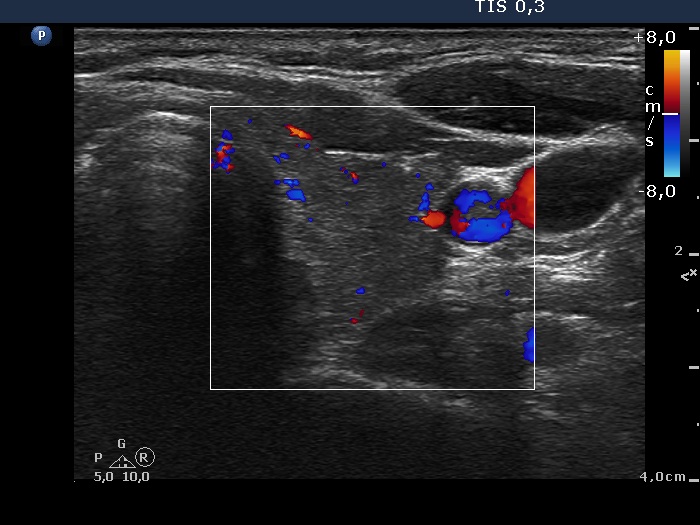

Ultrasonography: The thyroid was minimally-moderately hypoechogenic and presented fibrosis. There was a cystic lesion in the lower dorsal part of the right thyroid bed.

Further laboratory tests aTPO 308 U/mL, calcium 2.25 mM/L, phosphorus 1.11 mM/L, parathormone 40.9 pg/mL (normal range: 10-65). The parathormone content of the cystic fluid was 383 pg/mL.